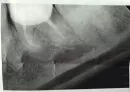

Коронка установлена 8 месяцев, и уже продолжительное время чувствую дискомфорт в десне, когда жуёшь на ней появляется неприятный привкус. Обращалась в несколько клиник, в том числе, где устанавливала коронку, уверяют, что ничего страшного нет, и пока ходить с ней, ничего не делать. Посмотрите пожалуйста снимок.

На корнях зуба имеется воспаление.

Лучше будет удалить зуб, дождаться заживления, восстановления костной ткани, и потом протезировать зуб , путем дентальной имплантации.